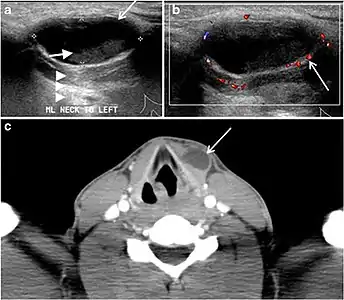

Fig. 8. A 48-year-old male patient post total thyroidectomy with PTC recurrence. a Transverse greyscale ultrasound of the neck demonstrates a left thyroid bed heterogeneous, predominantly hypoechoic irregular lesion with calcifications (white arrow). b A spot image of iodine 123 total body scan of the neck demonstrate a focus of abnormal radiotracer uptake at the left thyroid bed (Black arrows) between the annotated markers. c Enhanced axial CT scan of the neck demonstrates an enhancing large left thyroid bed mass (white arrow) with no calcifications. The lesion exerts a mass effect on the oesophagus (black arrow) and is inseparable from the trachea.[1]